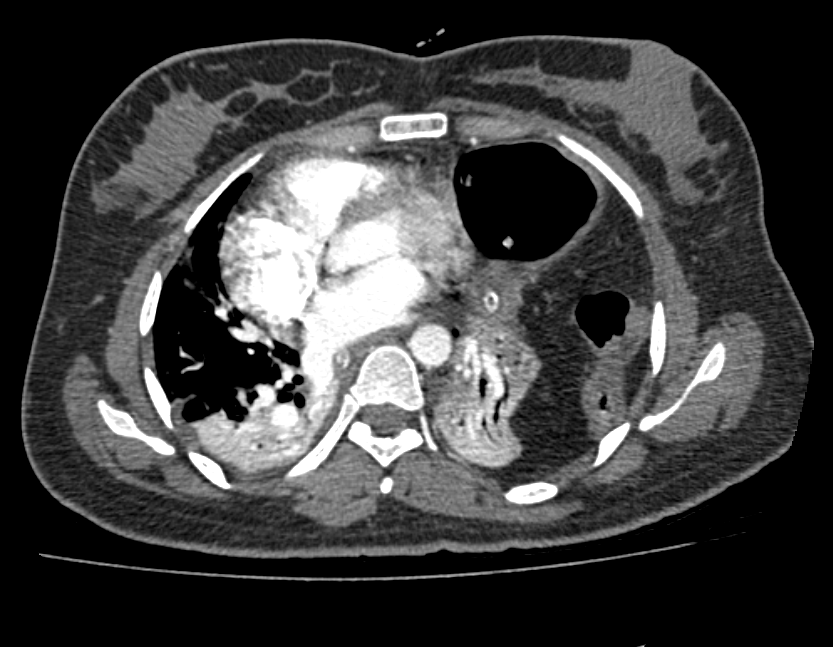

Figure 3. Surgeon's view through a left poetrolateral thoracotomy. Babcock grasping the stomach surrounded by omentum.

The patient was urgently taken to the operation theater and a left posterolateral thoracotomy incision was placed. After dividing the subcutaneous fat and muscle, the seventh intercostal space was entered. Contents of the hernia were visualized in the chest cavity and were manually reduced using digital compression. A loop-shape defect measuring approximately 15 cm in length was identified in the anterolateral part of the muscular portion of the diaphragm. The defect was repaired in three layers using a Prolene® 1 suture in a continuous fashion.